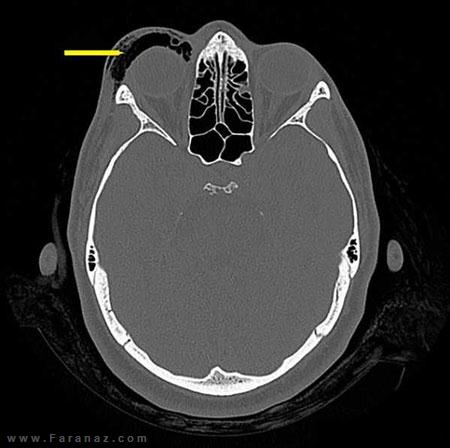

آزمایشات دقیق و عکسبرداری ها ثابت کرد که این زن دچار مشکل " آمفزیم مداری" شده . آمفیزم مداری یعنی تورمی که در هنگام خارج شدن هوا با شدت از بینی به داخل بافت نرم اطراف چشم فشار وارد می شود بروز می کند. در موارد شدید این مشکل می تواند با وارد کردن صدمه به سیستم عصبی چشم موجب کوری شود.